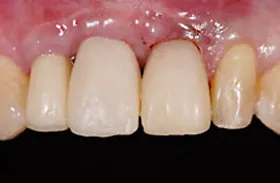

■治療後

治療のポイント

歯の根の位置を引き上げ、抜歯。その日にインプラント治療へ。

自然の歯と変わらない審美性を取り戻し、非常に満足されています。

| 主訴 | 上顎の真ん中の歯が折れた |

| 治療方法 | 歯の根を引き上げることにより、増骨するので、その後1本のインプラントを埋入し治療した |

| 治療期間 | 約1年 |

| 通院回数等 | 10回 |

| 費用 | 550,000円(税込) |

| リスク・副作用 | 外科治療なしで増骨させた為、治療期間が長くなった |